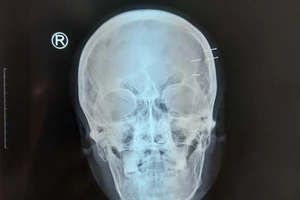

Tự bắn 4 cây đinh vào hộp sọ để giải sầu